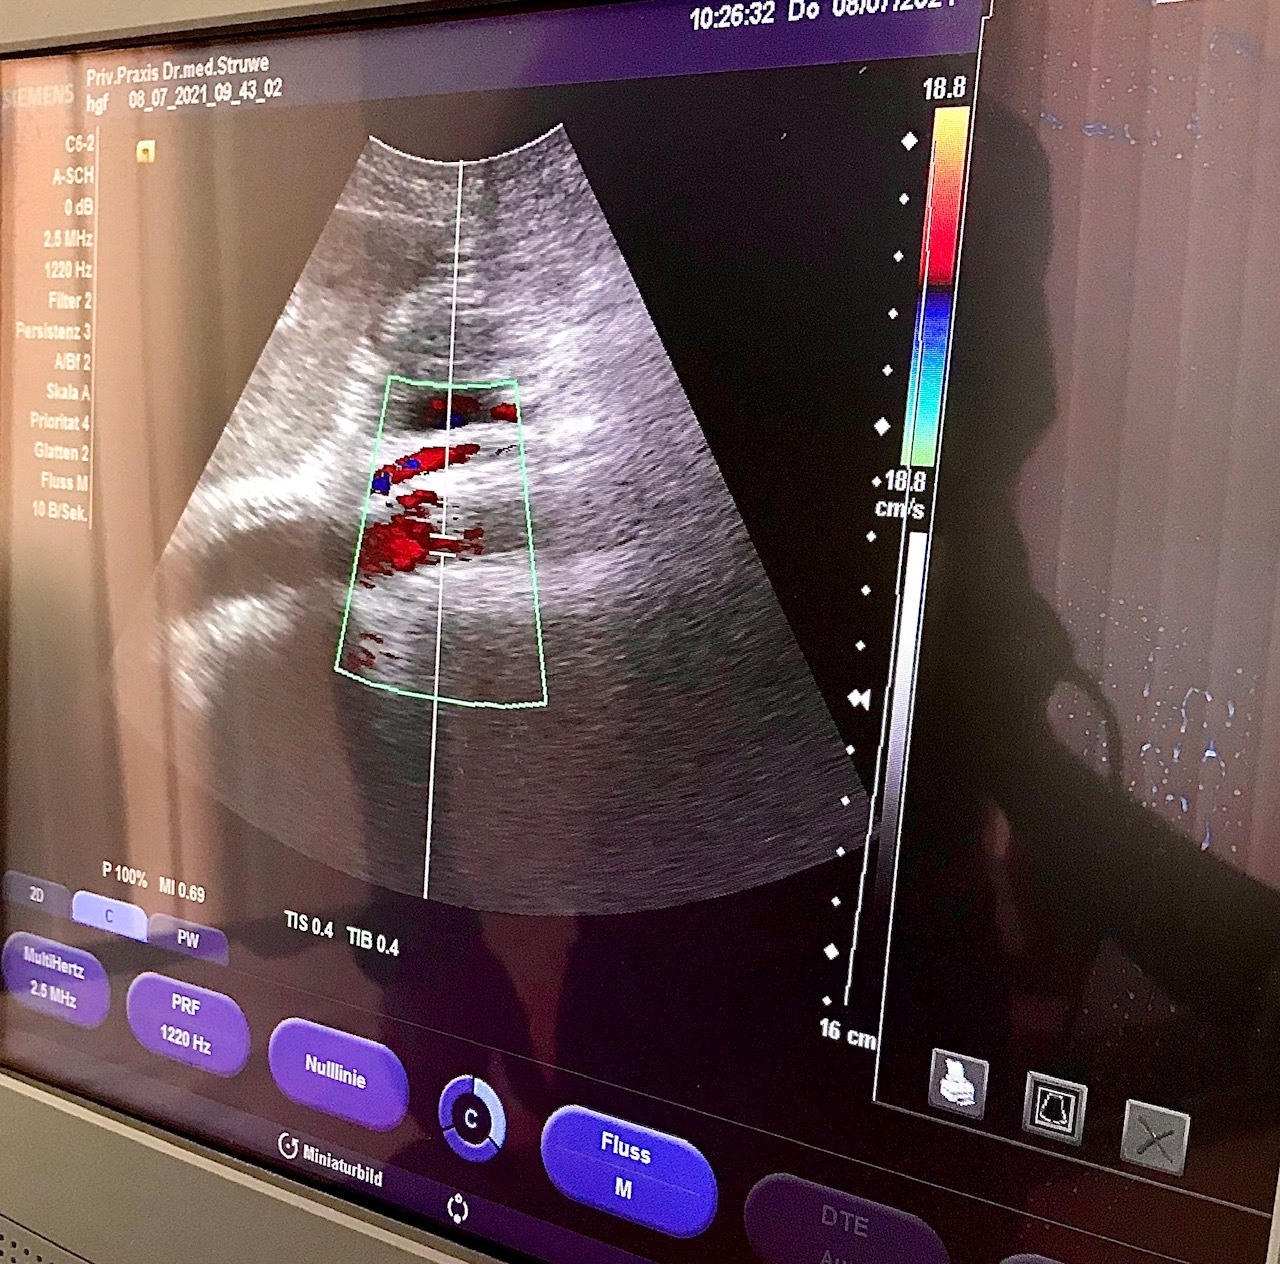

Ultraschall Organe - Medizinischer Check-Up für Sportler | SCHORK Sports & Dr. Otto Struwe, Freinsheim

- Gefäß- und Organ-Checks: Ultraschalluntersuchungen (je nach Umfang: Ultraschall Herz, Oberbauch, hirnzuführende Arterien und Schilddrüse, Bauch-  und Nierengefässe, Hirnbasisarterien)

Umfangreicher Gefäße & Organ-Check nach Absprache z.B. Oberbauch, Schilddrüse, hirnzuführende Arterien, Bauch-  und Nierengefässe.